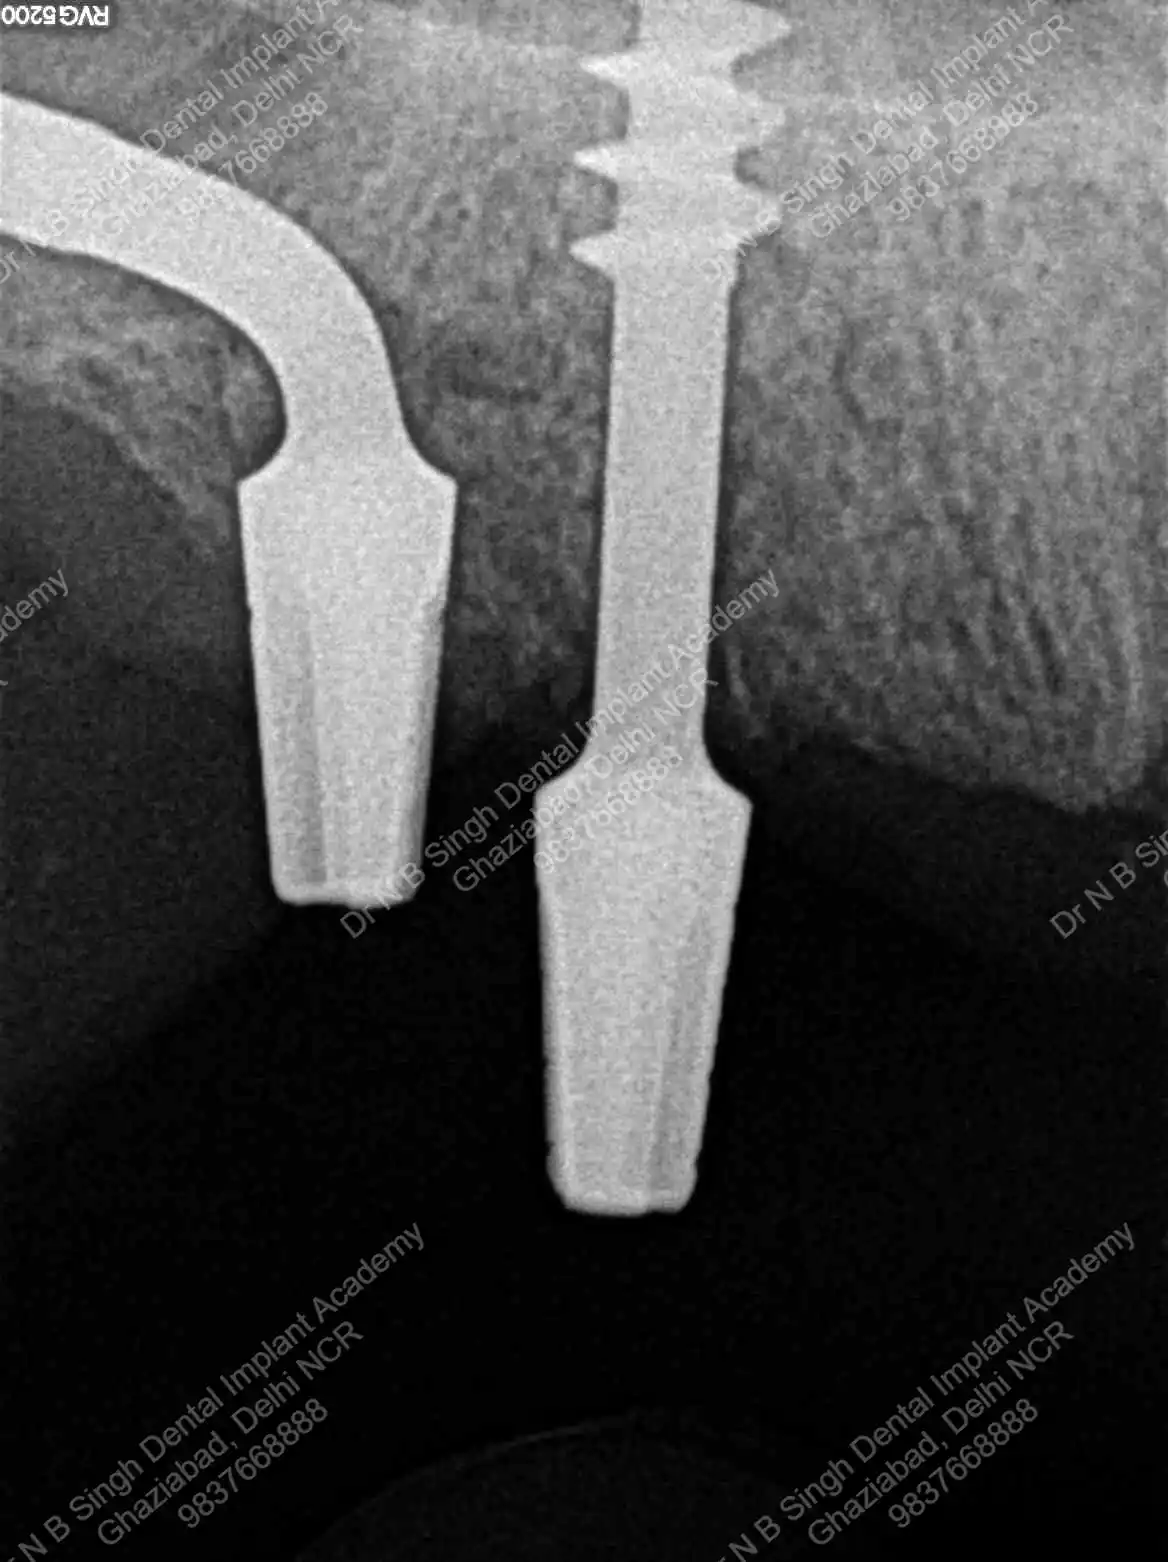

A008 Basal implants – af-qurs 1

Dr. N.B. Singh